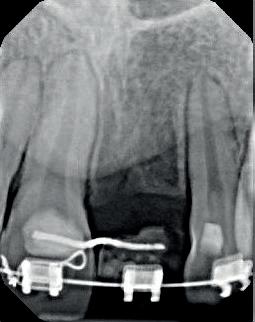

RECONFIGURAREA suportului osos implantar. În cazul prezentat, după ani de terapie ortodontică incorect executată, dezvoltarea dentară a pacientului a complicat obținerea unui zâmbet estetic. S-a reanalizat și s-a optat pentru abordare interdisciplinară care cuprinde chirurgia parodontală, un al doilea tratament

ortodontic și protetica pentru a oferi îngrijirea comprehensivă.

De asemenea, trebuie evaluate anual modificările radiografice. În ședința de inserție a restaurării, se înregistrează o radiografie bitewing standardizată pentru a permite evaluarea anuală a modificărilor osoase din jurul implantului. Remodelarea osului alveolar în primul an este bine documentată și depinde de tipul de implant utilizat; cu toate acestea, nu ar trebui să apară apical de primul filet al implantului. Prin urmare, este importantă abilitatea de a vizualiza filetele implantului pe radiografii. Modificările pierderii osoase de 2 mm sau mai mult după primul an reprezintă un semn de periimplantită. De îndată ce pierderea osoasă este recunoscută, pacientului trebuie să i se recomande terapia imediată pentru a opri procesul de boală.